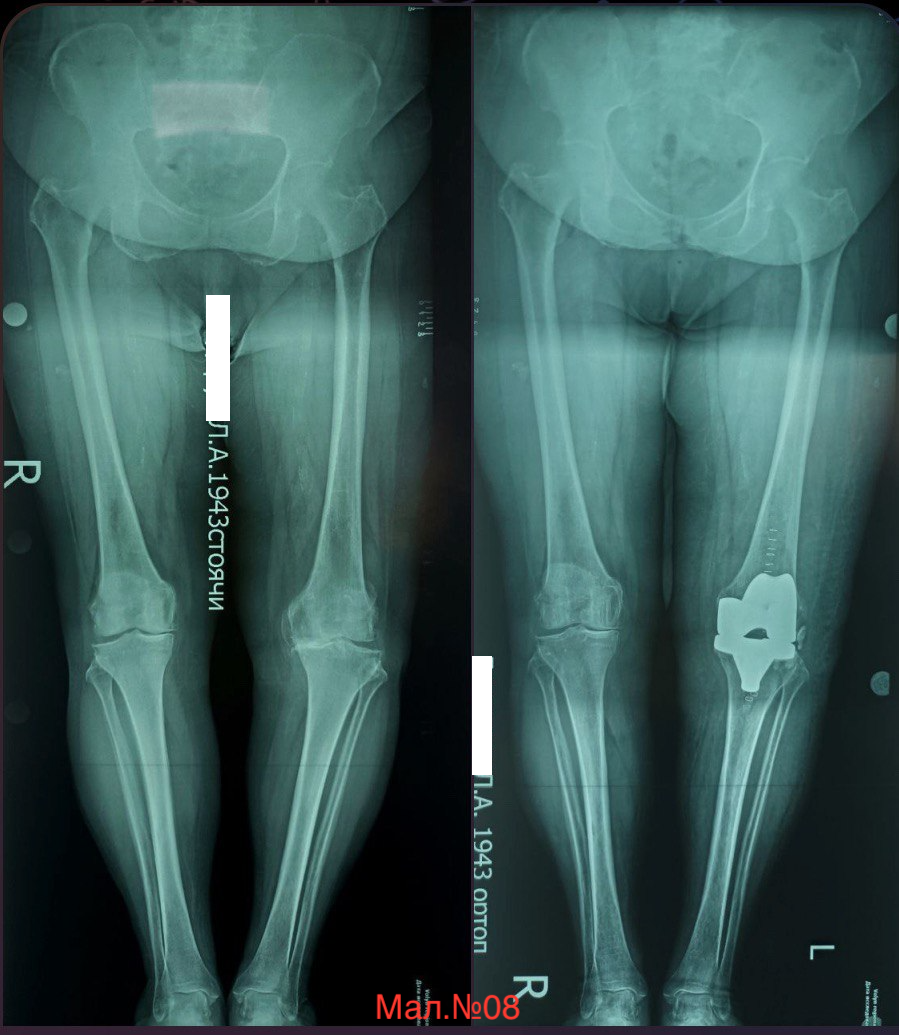

photo_2023-12-13 17.19.56